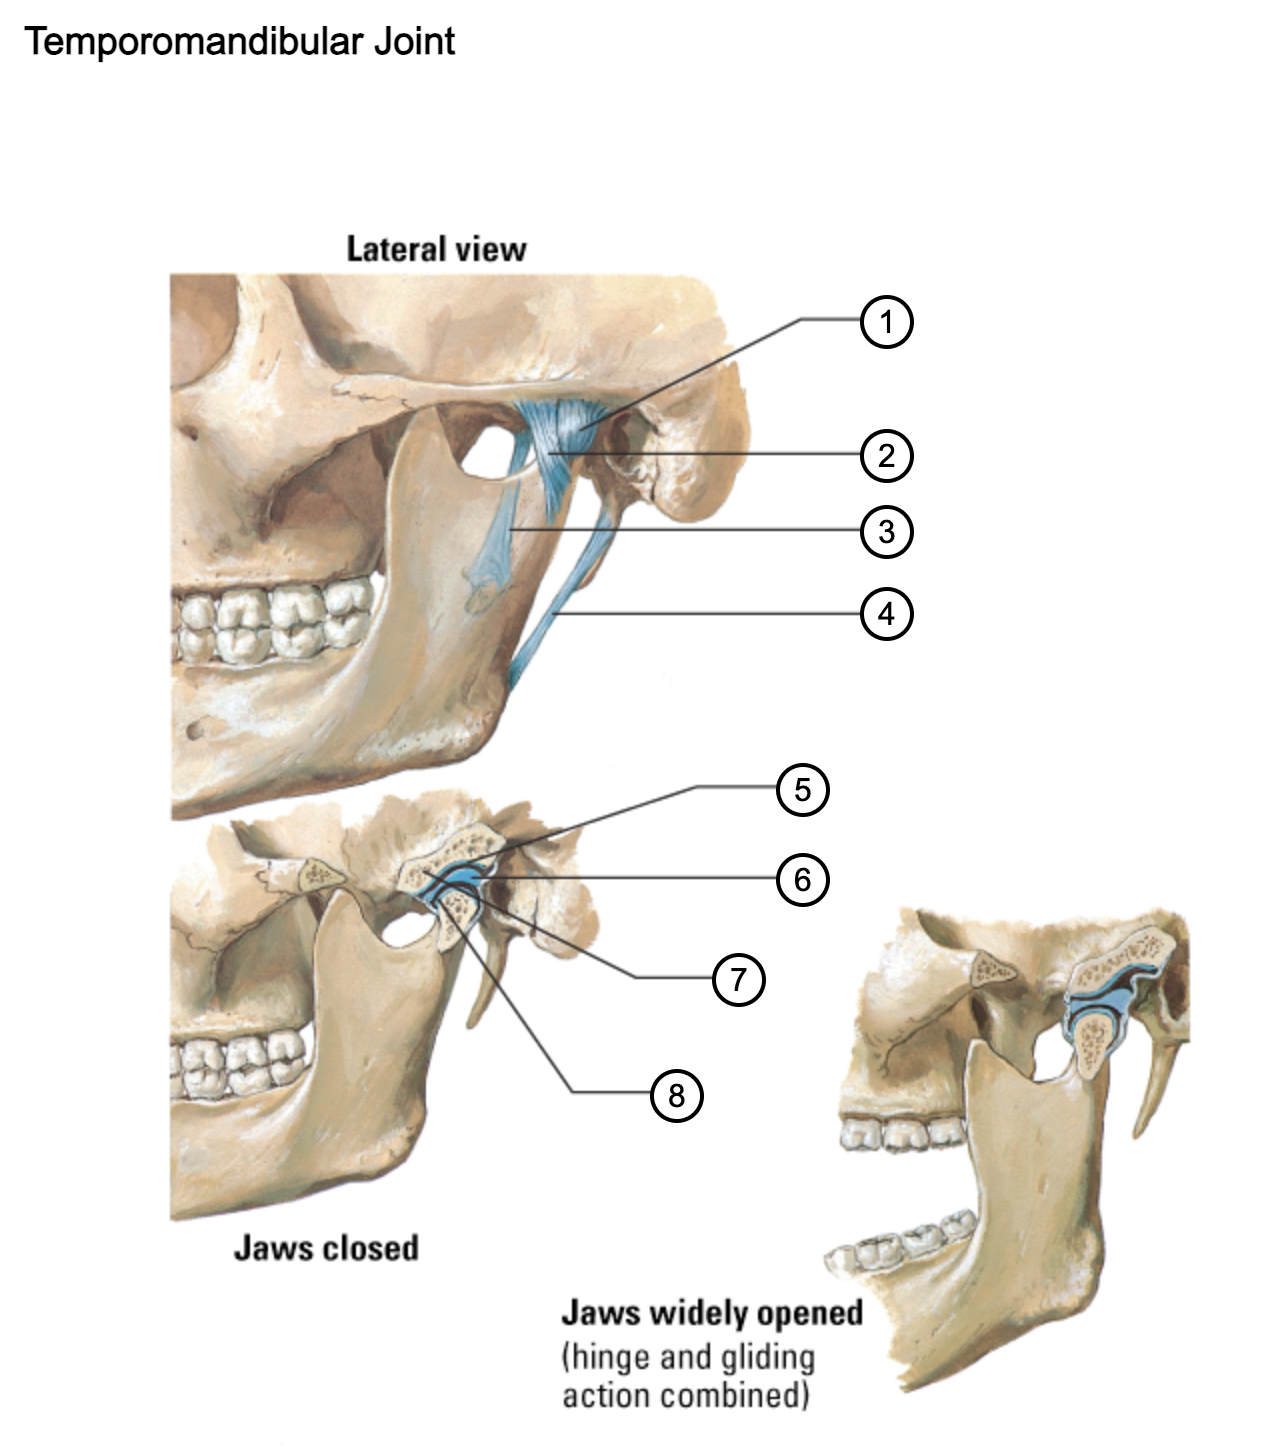

1

capsule of temporomandibular joint

2

lateral temporomandibular ligament

3

sphenomandibular ligament

4

stylomandibular ligament

5

mandibular fossa

6

articular disc

7

articular tubercle

8

capsule of temporomandibular joint